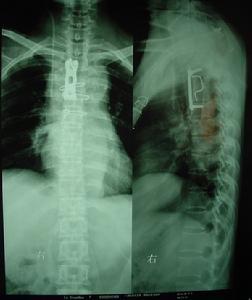

腰椎小关节(facet joint of lumbar)不稳症[1]指因外伤,退行性改变及先天发育等因素造成腰椎小关节不稳(又称为小关节半脱位或小关节错位),并引起腰痛、活动受限及其他一系列症状者;此时大多合并滑膜嵌顿,卧床休息可改善症状,一般多可治愈。